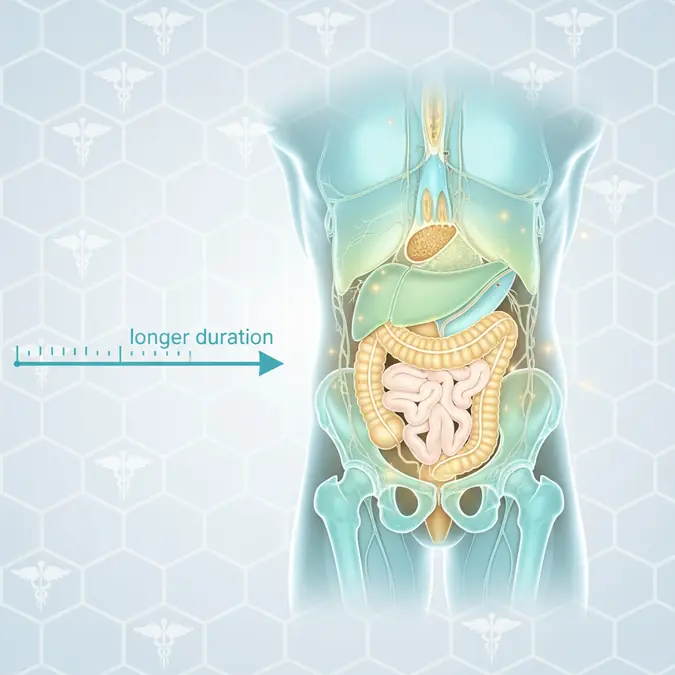

Preparaty, leki i suplementy na potencję

Przedwczesny wytrysk to powszechny problem, który można skutecznie kontrolować. Odkryj oparte na dowodach metody behawioralne, psychologiczne i medyczne, które pomogą Ci odzyskać kontrolę i czerpać więcej satysfakcji z życia intymnego.